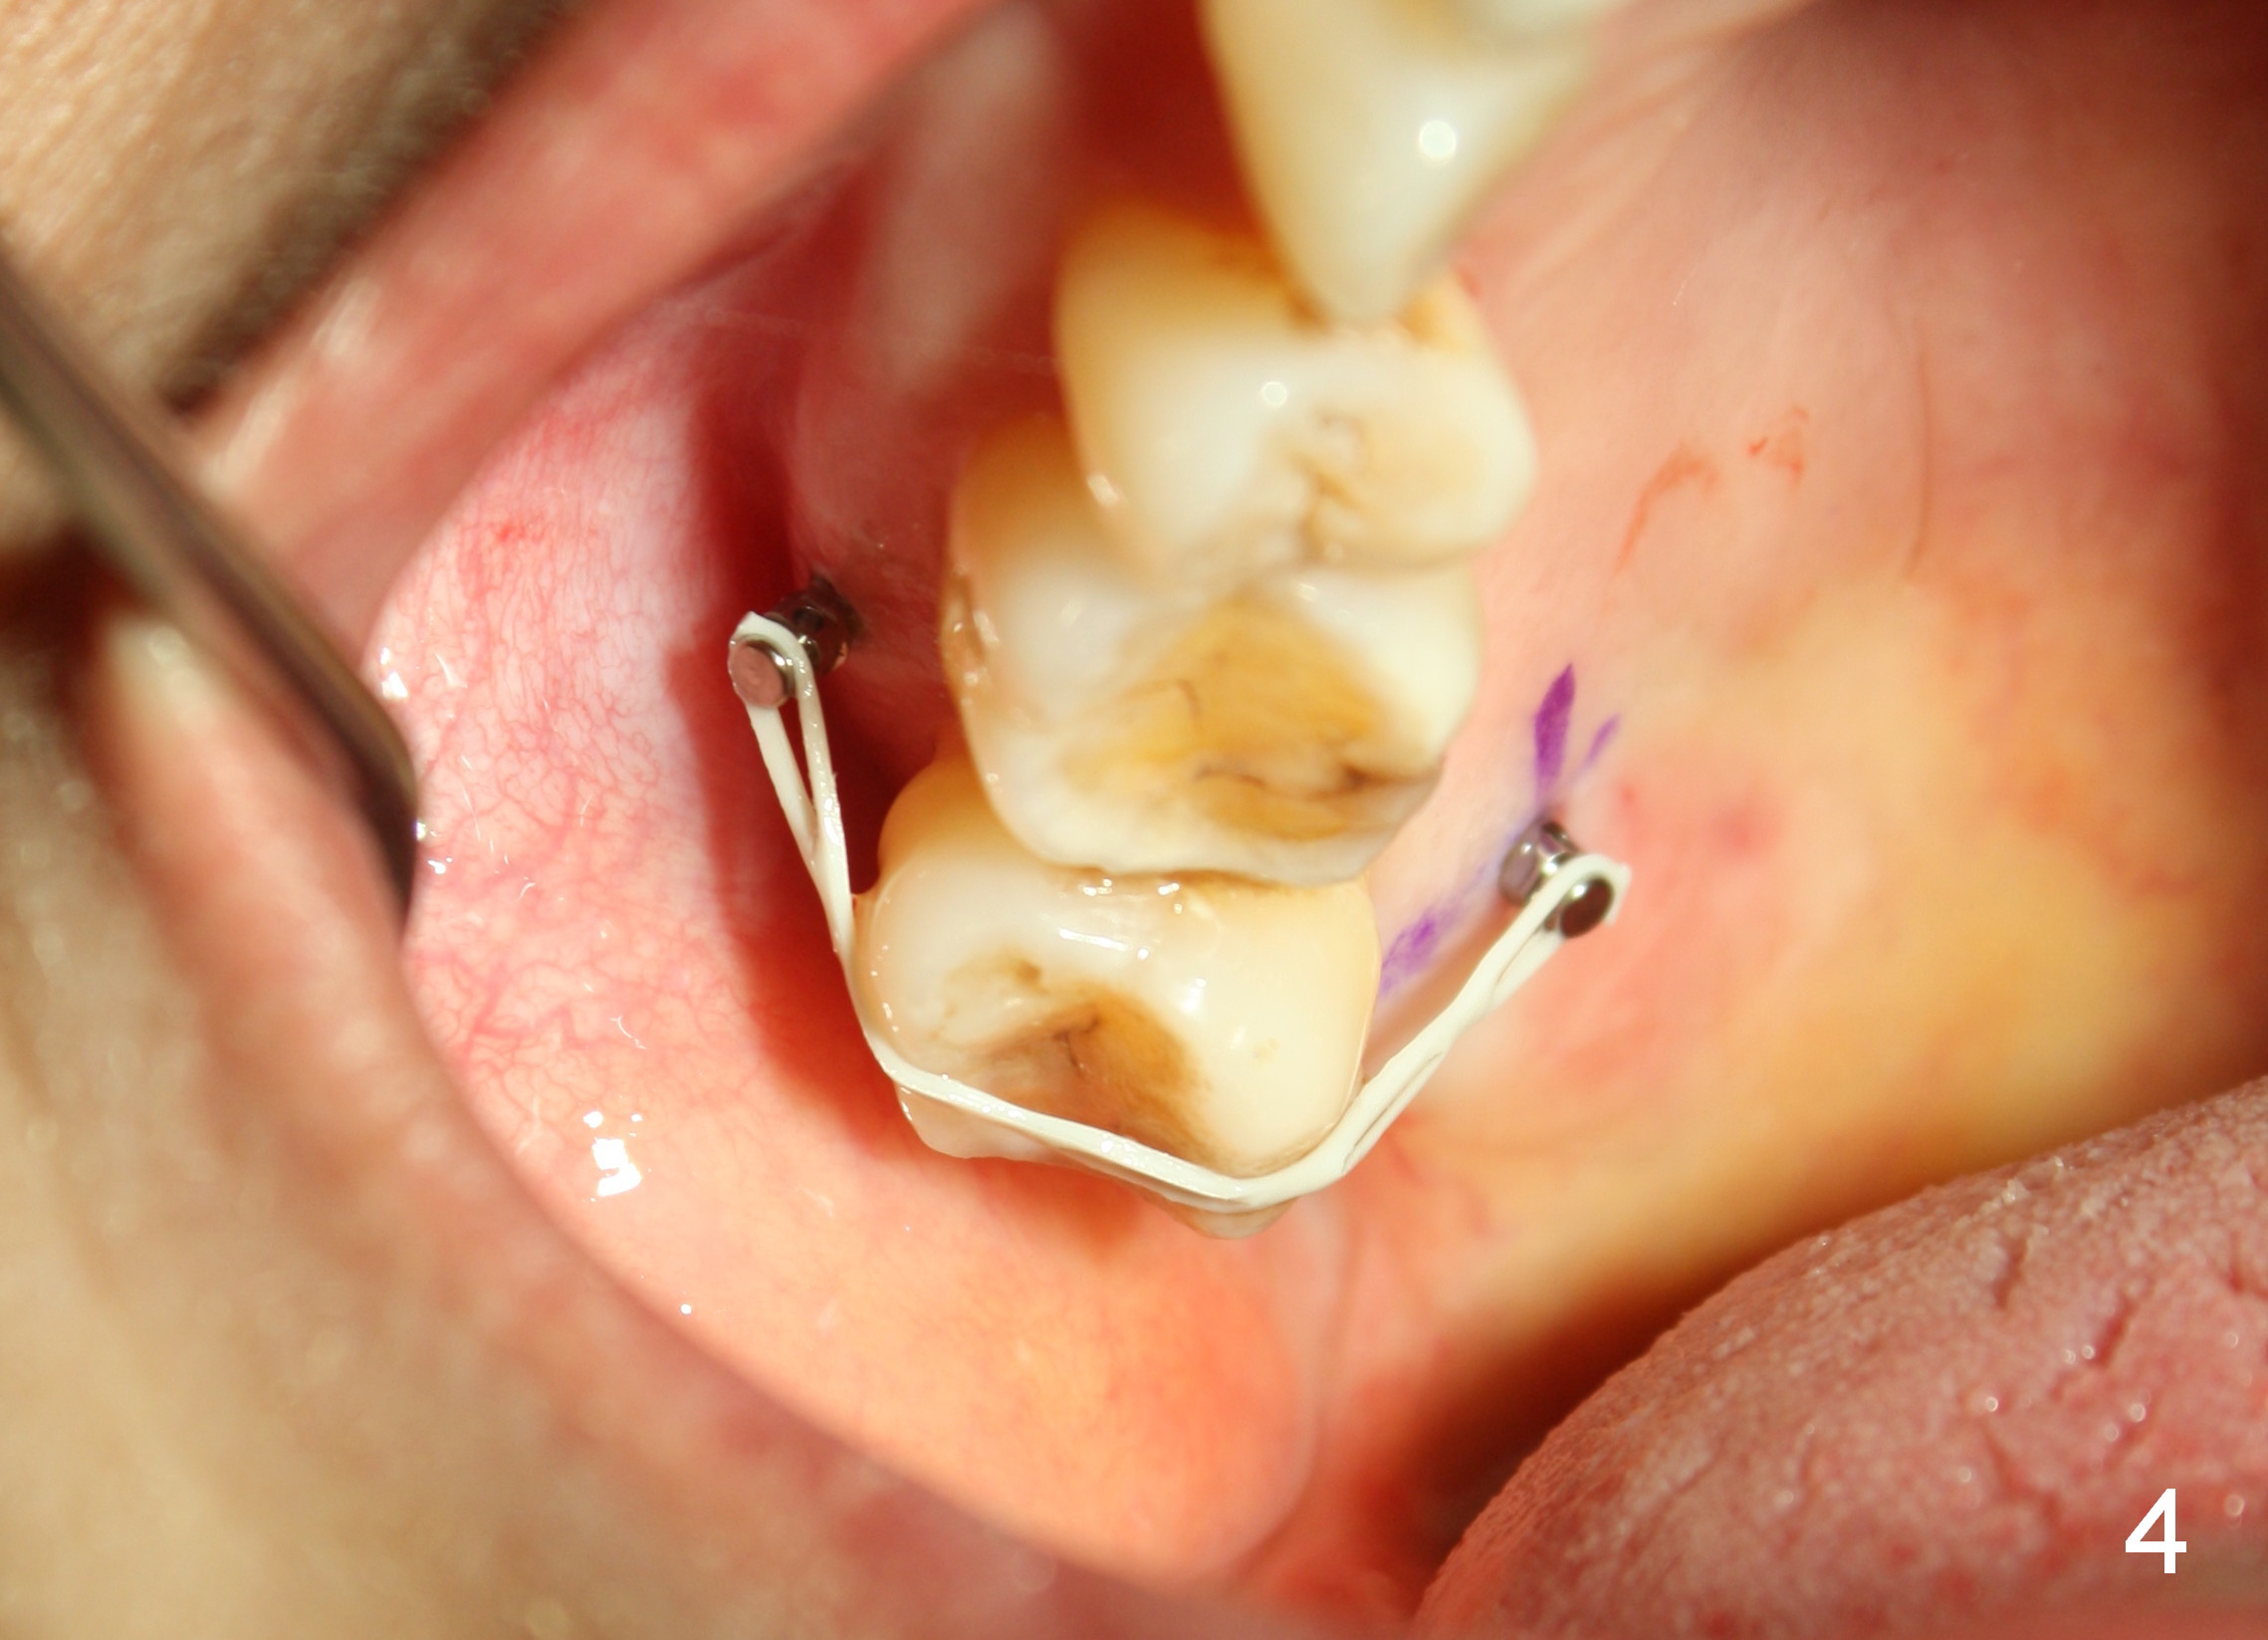

The wound of 2 stage implant surgery is found to be gapping 10 days postop with healing screw exposure 2 weeks postop. Exam at a month postop (Fig.1) shows that the mesiolingual cusp of the upper right 2nd molar is sharp (Fig.2 <) and inserted into the wound of the implant site (Fig.3). Two mini-implants are placed with immediate power chain retraction (Fig.4). The orthodontic intrusion is without effect; brackets are placed 4 months later (Fig.5). Two months later, the patient is diagnosed to have breast cancer. As a precaution for chemotherapy, the orthodontic device is removed. During chemotherapy, the patient returns once. The gingiva around the cover screw is mildly erythematous and edematous. After removing plaque from the cover screw with irrigation, the patient feels a little better. All of the orthodontic appliances are removed before she receives chemotherapy for breast cancer.